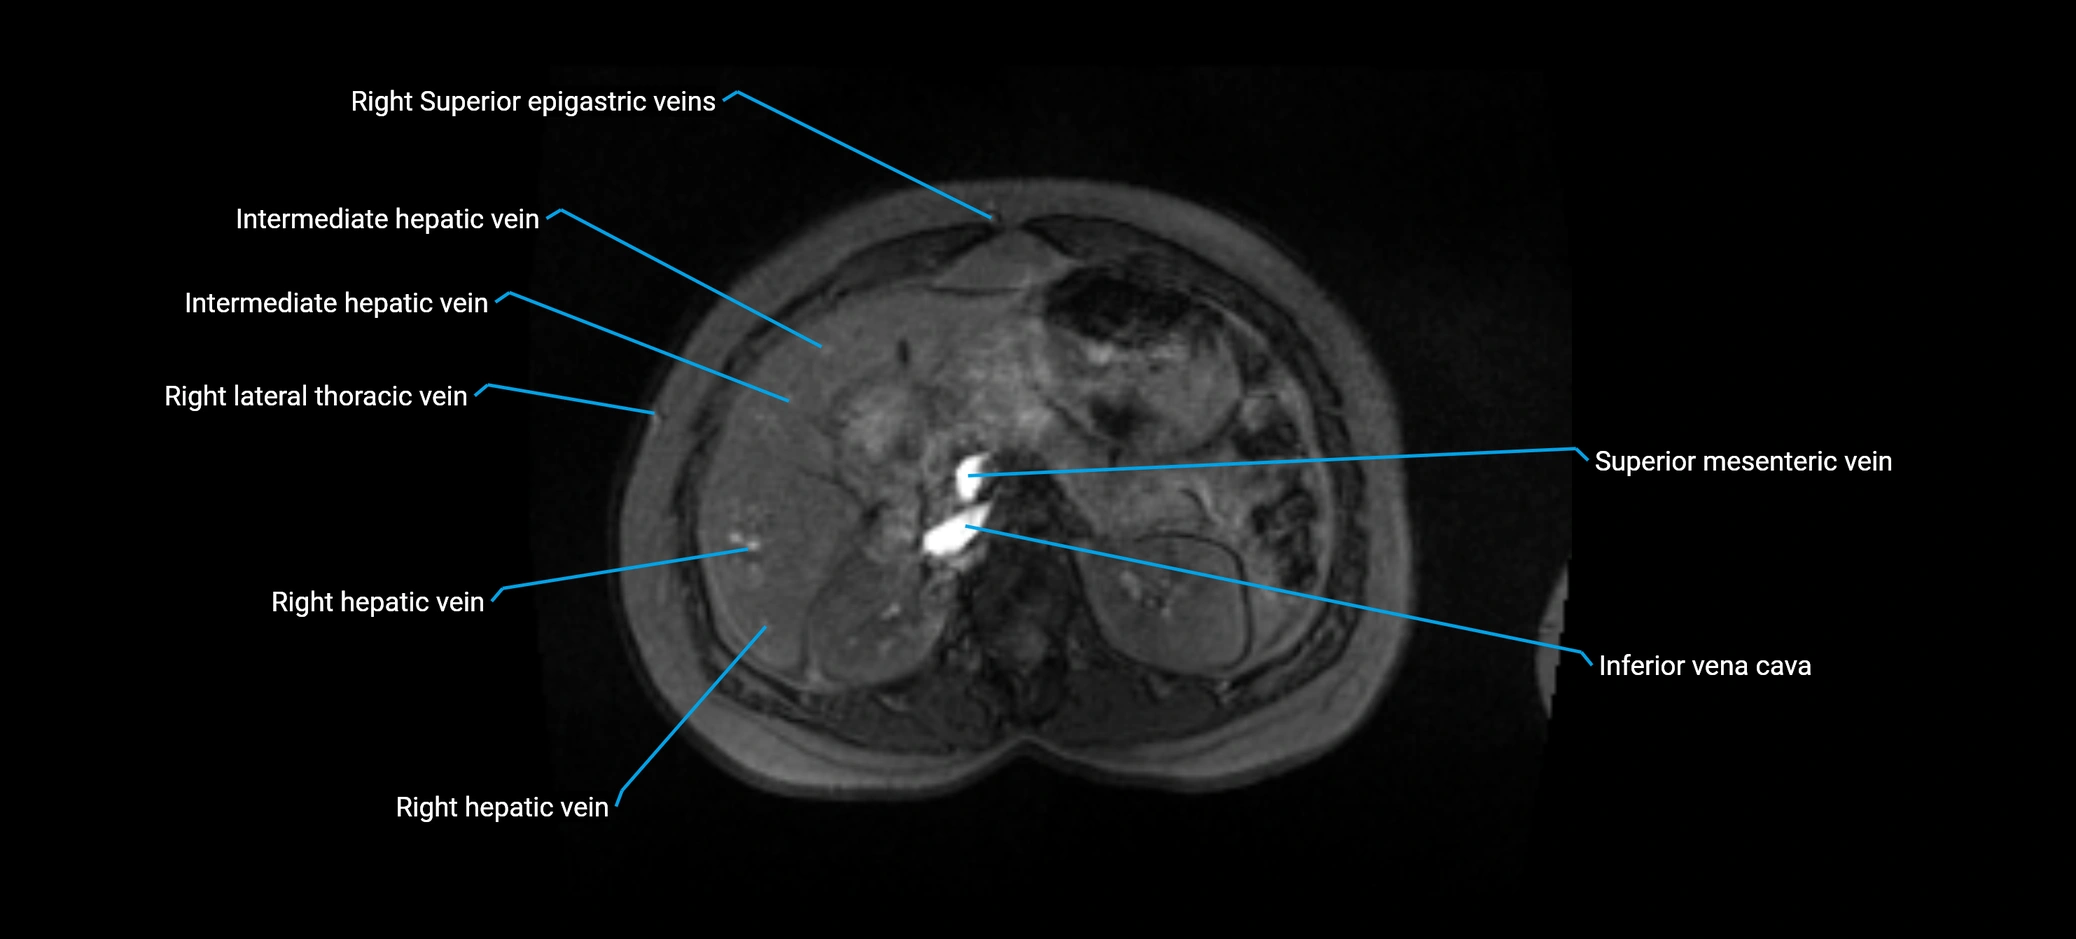

MRI image

image